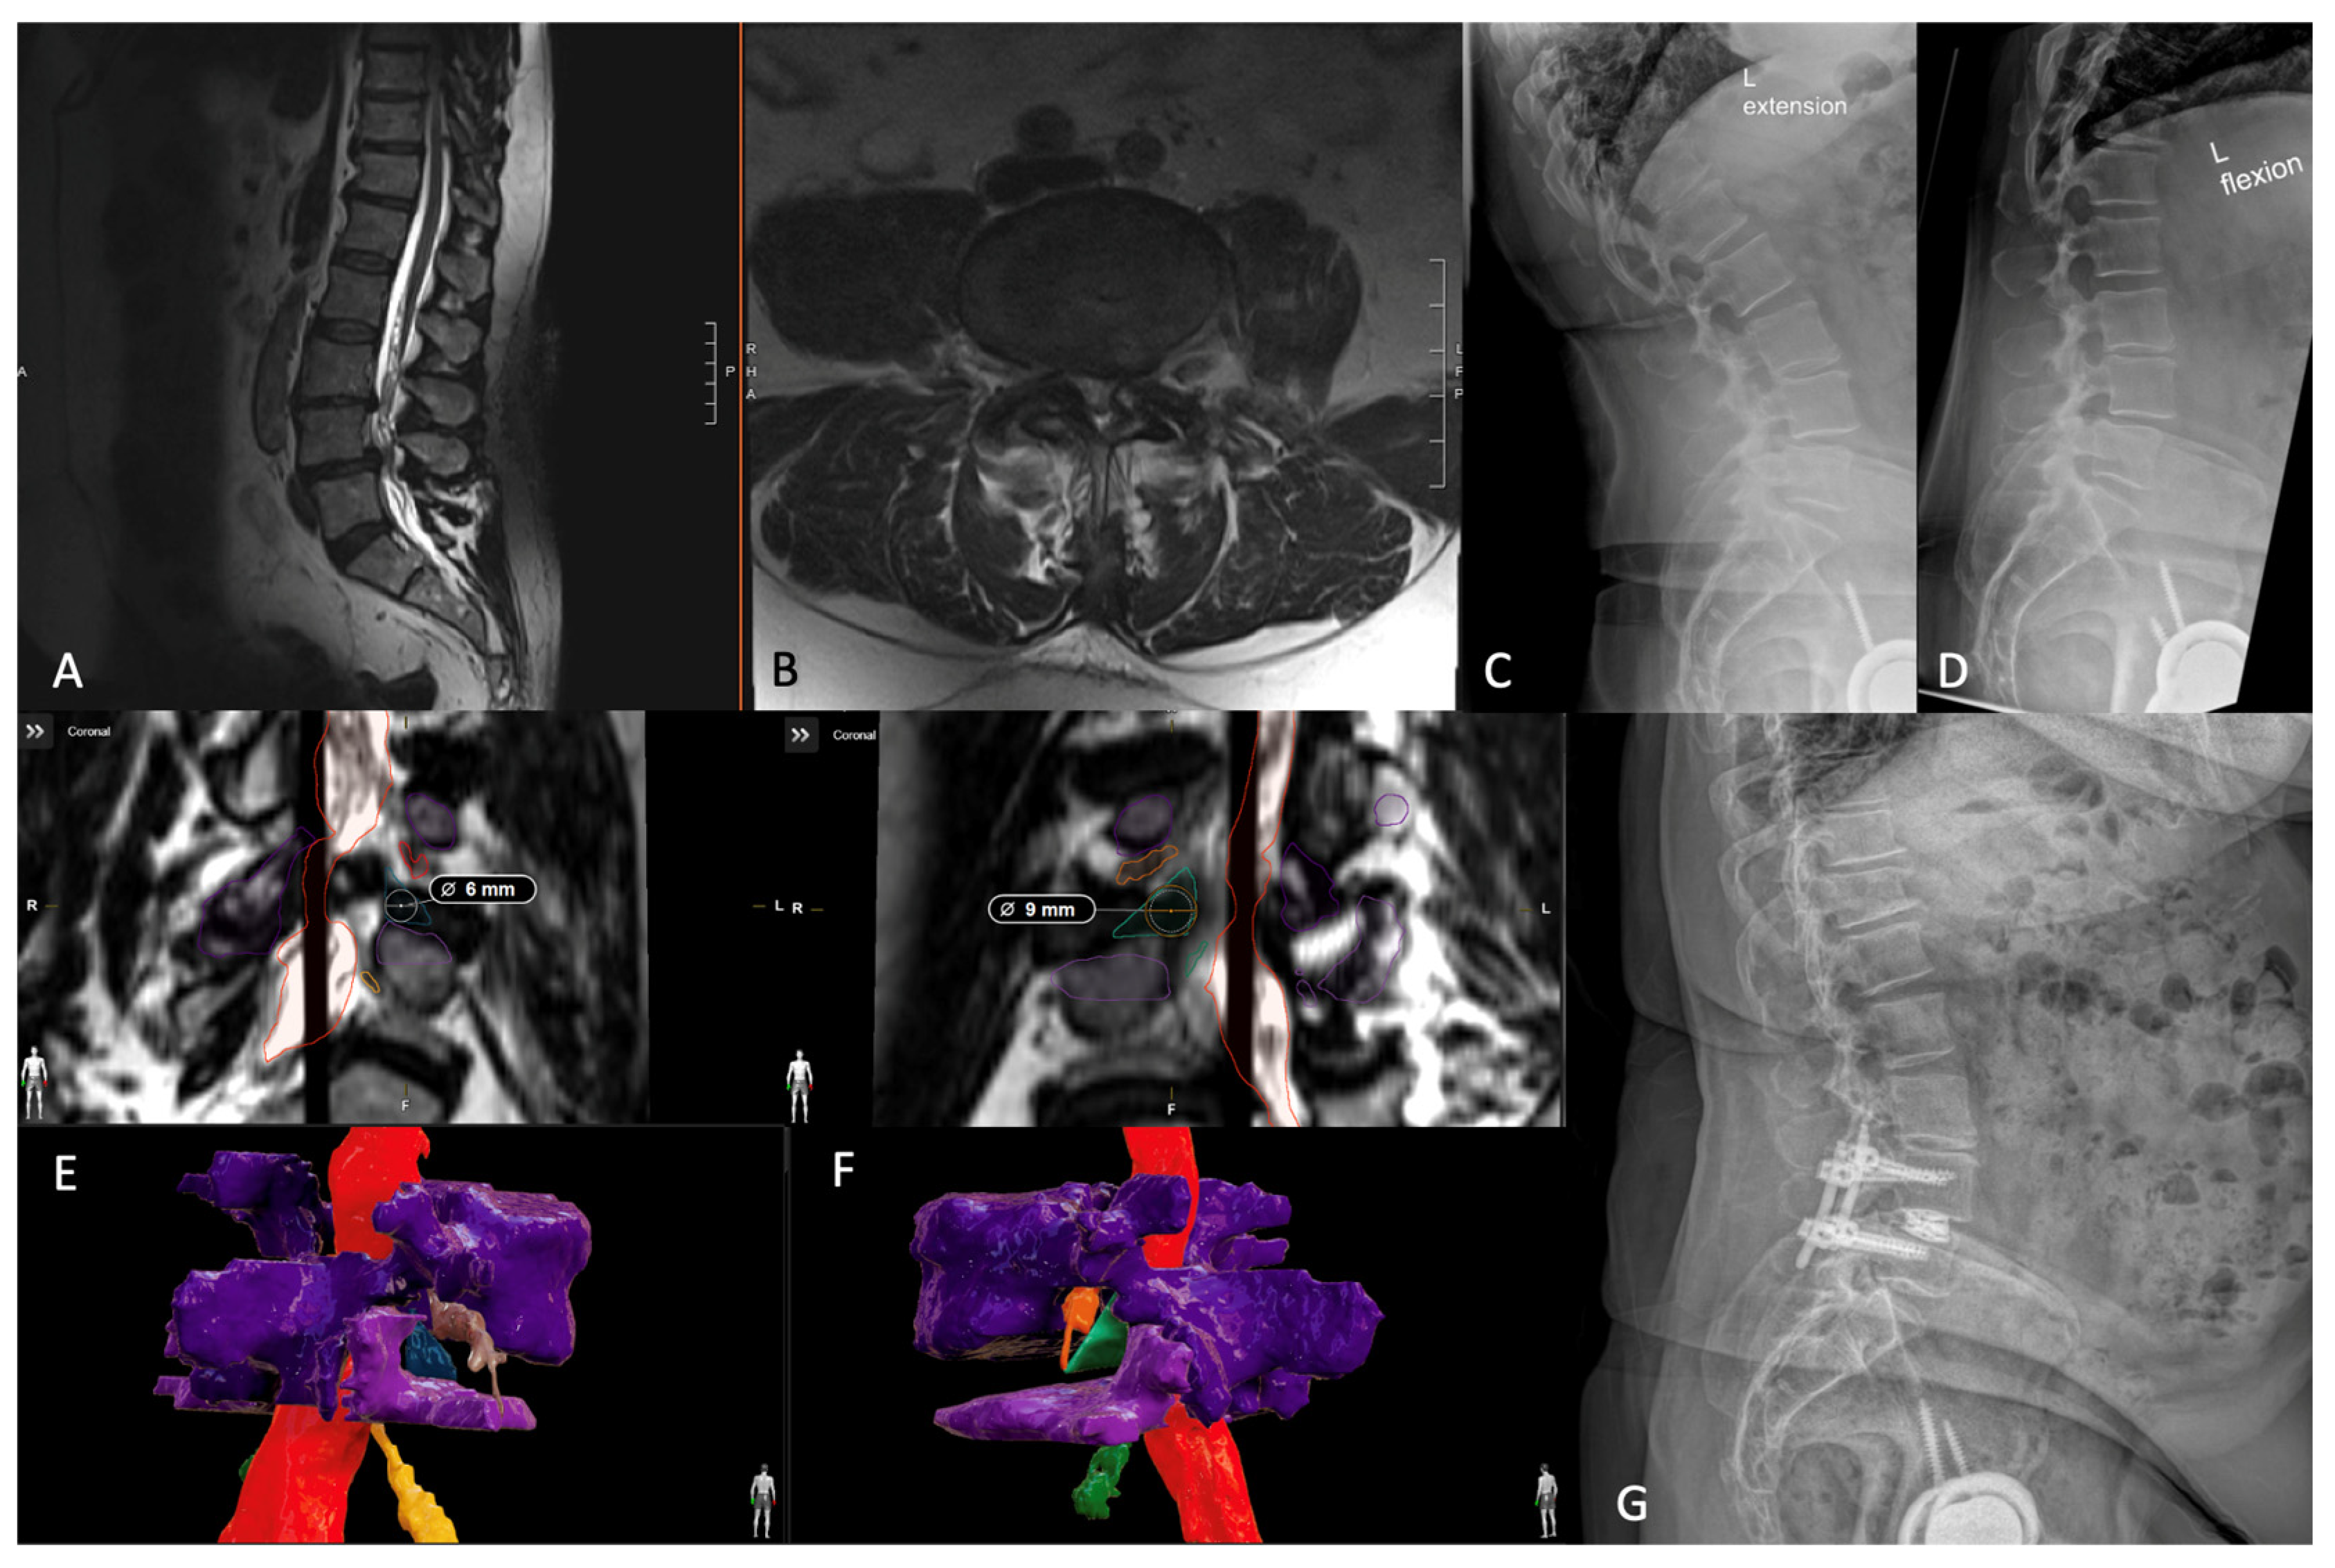

7. Patient-Specific Lumbar Interbody Fusion

7.1. Introduction

7.2. Three-Dimensional Neurosegmentation

- Tabarestani, T.Q.; Salven, D.S.; Sykes, D.A.W.; Bardeesi, A.M.; Bartlett, A.M.; Wang, T.Y.; Paturu, M.R.; Dibble, C.F.; Shaffrey, C.I.; Ray, W.Z.; et al. Using Novel Segmentation Technology to Define Safe Corridors for Minimally Invasive Posterior Lumbar Interbody Fusion. Oper. Neurosurg. 2023. [Google Scholar] [CrossRef] [PubMed]

- Tabarestani, T.Q.; Sykes, D.A.W.; Kouam, R.W.; Salven, D.S.; Wang, T.Y.; Mehta, V.A.; Shaffrey, C.I.; Wiggins, W.F.; Chi, J.H.; Abd-El-Barr, M.M. Novel Approach to Percutaneous Lumbar Surgeries via Kambin’s Triangle-Radiographic and Surgical Planning Analysis with Nerve Segmentation Technology. World Neurosurg. 2023, 177, e385–e396. [Google Scholar] [CrossRef] [PubMed]

- Tabarestani, T.Q.; Sykes, D.A.W.; Maquoit, G.; Wang, T.Y.; Ayoub, C.M.; Shaffrey, C.I.; Wiggins, W.F.; Abd-El-Barr, M.M. Novel Merging of CT and MRI to Allow for Safe Navigation into Kambin’s Triangle for Percutaneous Lumbar Interbody Fusion-Initial Case Series Investigating Safety and Efficacy. Oper. Neurosurg. 2023, 24, 331–340. [Google Scholar] [CrossRef] [PubMed]